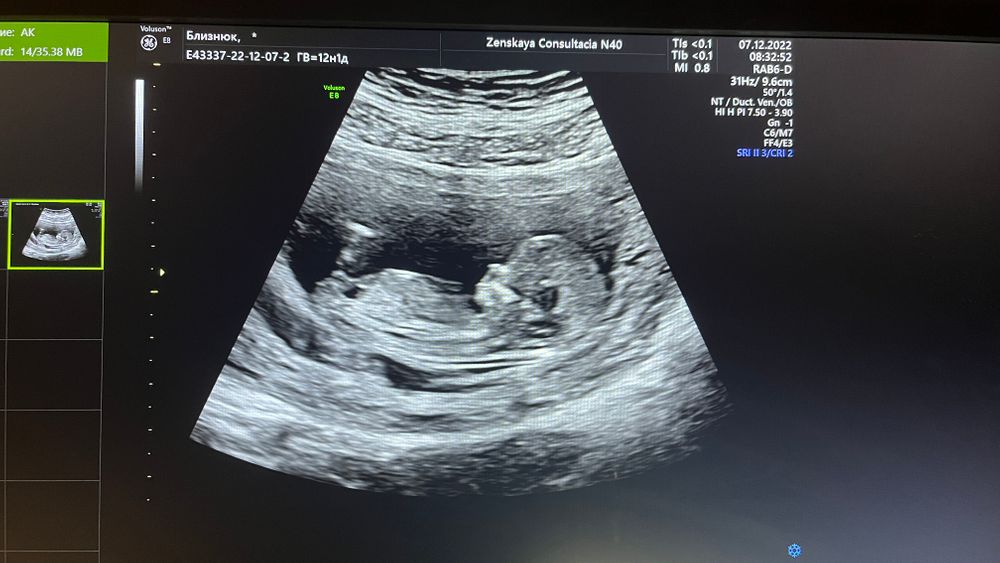

Алёнка, сомневаюсь, бугорок или нет в кадре. Если это он, то больше девичий)) Но вот не уверена прям, что это он. Ждём твой второй скрининг, если, конечно, раньше не пойдёшь, недель в 15-16, ради пола)) Можешь, конечно, девчонкам показать тут - может, разглядят 😊 В любом случае, очень милый профиль. Пусть растёт дальше здоровым ребёночком☺️

07.12.2022

Там ножка мешает точно глянуть, но предполагаю девочку по тазобедренной кости

На этом фото непонятно, там что-то ещё мешает, если половой бугорок, то что более белое и горизонтально, то девочка, а если то что прозрачнее и вверх торчит, то мальчик.

Nina, я думаю то, что более белое - бугорок.

Юлия Sonnце, мне показалось, что крупновато для бугорка, на голень больше похоже🙈

А какой срок? Мне кажется девочка

Женя, ну, 1 скрининг, 12 полных.

Женя, хотя непонятно, какой-то градус подъёма есть)

Женя, ну, вот и глаза ломаю)) С первого взгляда позалось, что девочка.

Здесь видно половой бугорок? Закрасила кружок💙